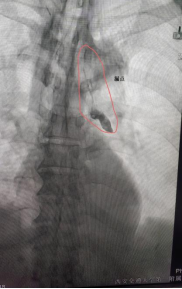

经介入手术室梅娜护士长,白婷副护士长协调下,我科汤瑞祥主治医师率先成功开展胸导管栓塞术。超声引导下细针穿刺双侧腹股沟淋巴结成功后,缓慢经淋巴结注入造影剂。造影剂下显露胸导管走行及漏点位置。DSA下经腹穿刺腹部淋巴管成功后置入导丝及微导管。于微导管内注入生物胶。注入完成后造影显示胸导管破损处栓塞确切。术后在科室护理人员精心护理下,患者介入后第2天引流液即转为正常并顺利拔除胸腔引流管。患者体表创伤仅为细针穿刺损伤。